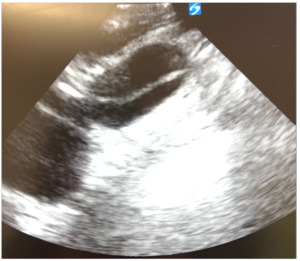

However, upon further careful medical history taking, the patient also reported chest pain that started that morning. He stated that the pain was located over the left side of his chest, felt sharp, was intermittent, but not worsened with exertion. He denied any recent upper respiratory infection, trauma to the chest, history of drug use, or previous history of chest pain.6 Although his blood pressure and heart rate were mildly elevated, his cardiac examination was normal, and he had good pulses in all of his extremities. We ordered tests to assess for potential acute coronary syndrome including electrocardiograms (ECG), high sensitivity troponins, and chest radiography. The ECG (Figure 2) showed sinus tachycardia at about 102 beats per minute, poor R wave progression across the precordial leads suggestive in this case of previous anteroseptal injury, and left ventricular hypertrophy per the modified Cornell criteria, but no ST segment elevations concerning for acute cardiac ischemia. The high-sensitivity troponin was very minimally elevated to 0.07 and downtrended to 0.06 three hours later. All other labs were grossly unremarkable besides mildly elevated liver function tests. The portable chest radiograph, however, showed a modestly widened superior mediastinum, as pictured in Figure 3. We quickly proceeded with a bedside ultrasound which showed a large ascending aortic aneurysm (Figure 4) with an associated proximal aortic dissection. In Figure 5, a dissection flap can be clearly visualized. After consulting with cardiothoracic surgery while starting the patient on an esmolol drip for blood pressure and impulse control, we obtained a CT angiogram of the chest which showed a 7.7 cm dissecting aneurysm involving the ascending aorta and proximal aortic arch with a large, partially thrombosed false lumen and extension into the proximal innominate artery (Figure 6). The radiologist also noted there was marked compression of the superior vena cava (SVC) due to the large aneurysm of the ascending aorta. The patient later required a nicardipine drip after high-dose esmolol failed to optimally control his hyperdynamic state.